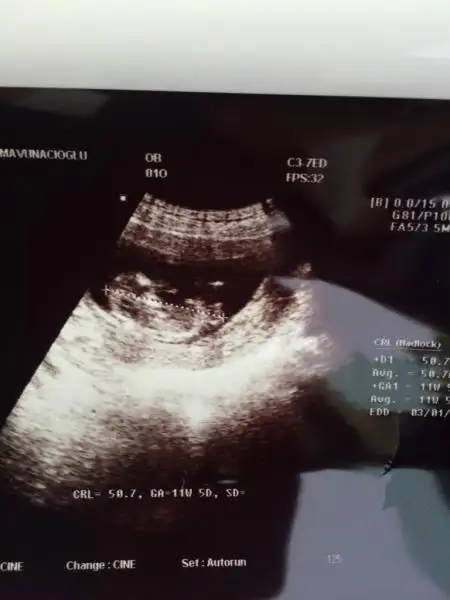

Benim 4 boyutlu değil ama bakabilirmisiniz nubuna. Şu an 13+0 Daha 10 gün var kontrole. Ilkinde 11 hafta 5 gün,ikincisinde 12 hafta 3 günlüktük.

$ImageUploadedByKadınlar Kulübü1403871661.181270.webp